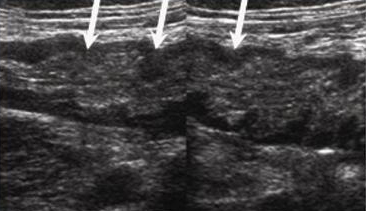

Colon : L'epaisseur du colon varie

entre 5mm et peristaltisme presque interceptible .

Colon droit : Les haustrations

sont plus espacees et la paroi anterieure presque

toujours aerique ** |

Colon gauche : Haustration sont plus nombreuse s avec hypertrophie

musculeuse |